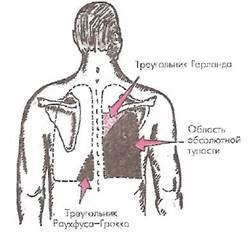

Обычно методом перкуссии можно выявить плевральный выпот, если его объем превышает 300-400 мл. При перкуссии в этой зоне определяется выраженное притупление перкуторного звука, а при значительной толщине слоя экссудата — абсолютно тупой («бедренный») звук. При умеренном количестве экссудата верхняя граница тапости проходит по линии Эллиса-Дамуазо

(рис. 16).

Рис. 16.

Изменение перкуторного звука при экссудативном плеврите.

Показаны область абсолютной тупости, соответствующая проекции плевральной жидкости на грудную стенку, треугольник Гарланда (область компрессионного ателектаза) и треугольник Раухфуса-Грокко (смещенное средостение)

Наиболее высокая точка этой линии располагается по задней подмышечной или лопаточной линии. Отсюда она спускается косо вниз, сзади пересекая позвоночник, а спереди доходя до срединно-ключичной линии па уровне V ребра.

Сзади выше верхней границы тупости располагается участок поджатого легкого — область компрессионного ателектаза. Он образует так называемый треугольник Гарлан

да,

ограниченный позвоночником, линией Эллиса-Дамуазо и горизонтальной линией, проходящей через ее верхнюю точку (см. рис. 16). Перкуторно здесь определяется притупление с тимпаническим оттенком. Притупление перкуторного звука связано с умеренным уплотнением поджатого легкого, а тимпанический оттенок указывает на сохранение некоторой воздушности легочной ткани в области компрессионного ателектаза и значительное снижение эластичности легочной ткани.

Наконец, если в плевральной полости скапливается значительное количество экссудата (более 4 л), перкуторно можно определить участок притупления, соответствующий проекции смещенного в здоровую сторону средостения {треугольник Раухфуса-Грокко).

Этот треугольник ограничен позвоночником и продолжением линии Эллиса-Дамуазо (см. рис. 16).